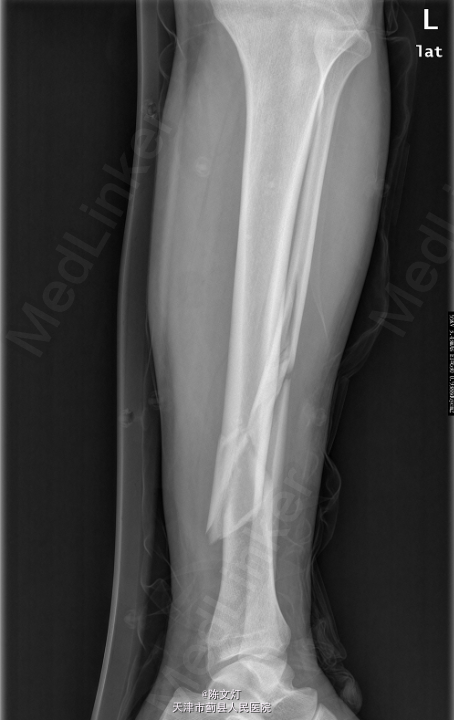

患者,男,36岁,因“车祸致左小腿疼痛伴活动受限1天”入院。

查体:左小腿活动受限,局部疼痛,皮肤感觉无殊,皮肤无破溃,趾端活动无殊,可及足背动脉搏动。其余肢体无殊,病理征未引出。辅助检查:2015-05-06 我院行CR检查提示:左胫腓骨骨折。